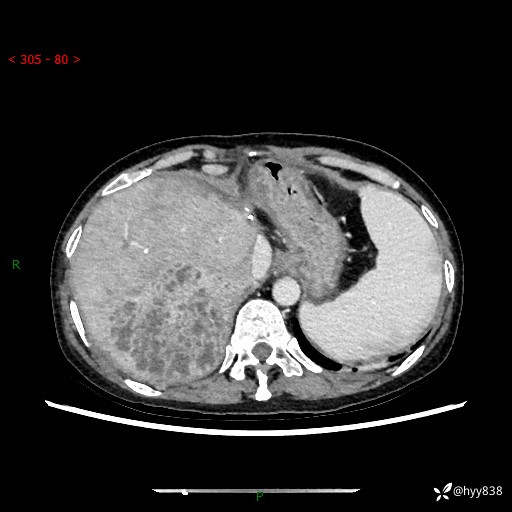

病例老年女性,发热来诊。如此“蜂窝煤”,治疗很棘手---结果公布~

性别:女

年龄:53岁

简要病史:发热(门诊急诊患者)

上腹部CT平扫